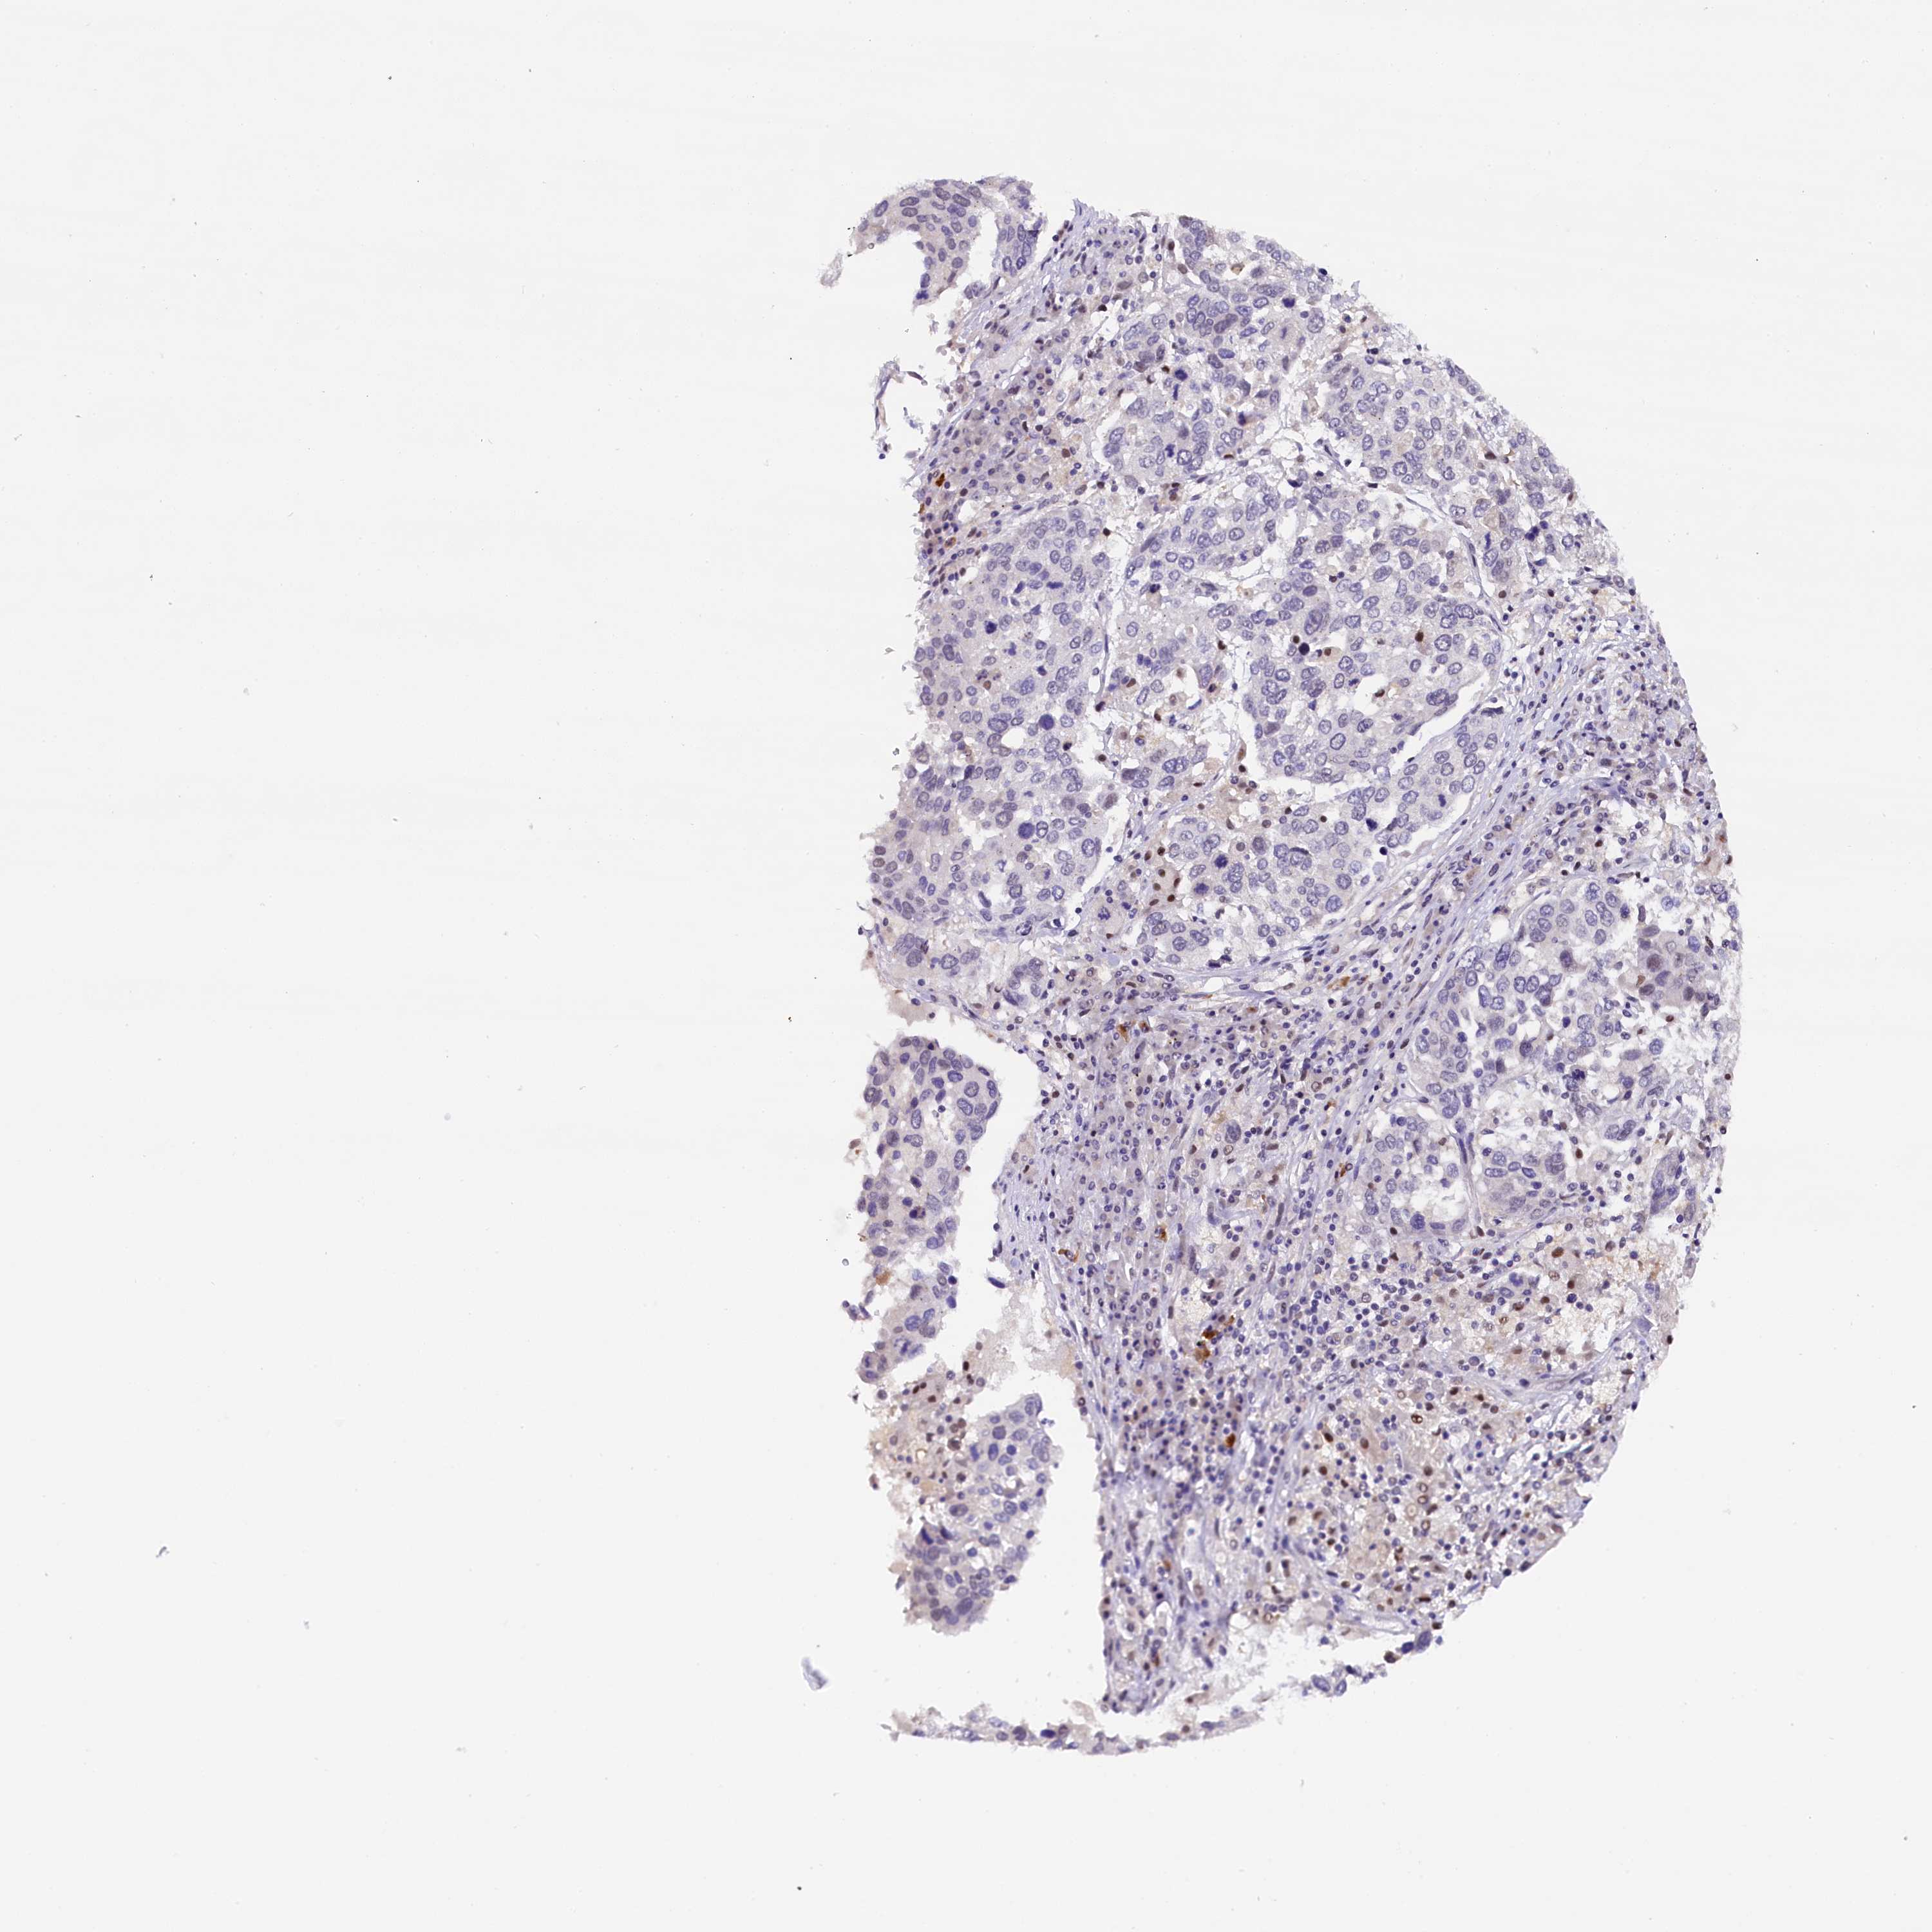

IQCN

CANCER LUNG CANCER Show tissue menu

LUAD TCGA LUAD VALIDATION LUSC TCGA LUSC VALIDATION PROTEIN LUAD CPTAC PROTEIN LUSC CPTAC PROTEIN EXPRESSION

ANTIBODIES

AND

VALIDATION